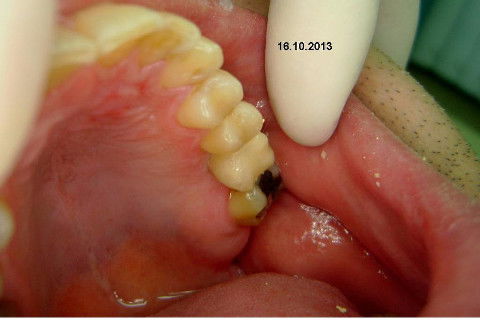

Instalação de um implante em região do 26. Utilizamos um implante cone morse Alvim Neodent 4.3 X 11,5. Foi uma cirurgia muito rápída e minimamente traumática, sem retalho e sutura.